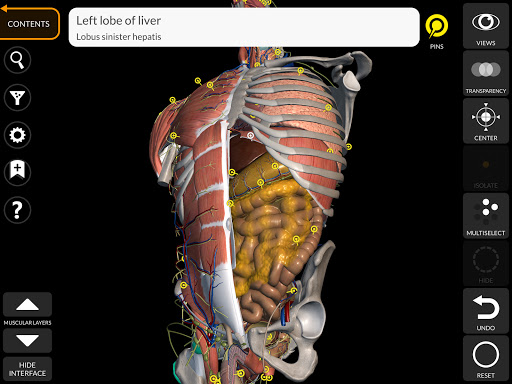

"Anatomy 3D Atlas" vous permet d'étudier l'anatomie humaine de manière simple et interactive.

Grâce à une interface simple et intuitive, il est possible d'observer chaque structure anatomique sous n'importe quel angle.

Les modèles anatomiques 3D sont particulièrement détaillés et avec des textures jusqu'à une résolution de 4k.

La subdivision par régions et les vues prédéfinies facilitent l'observation et l'étude de parties individuelles ou de groupes de systèmes et les relations entre différents organes.

• Fonction de recherche pour trouver facilement chaque partie anatomique

• En sélectionnant un modèle ou une épingle, le terme anatomique associé apparaît

• Les termes anatomiques peuvent être affichés en deux langues simultanément